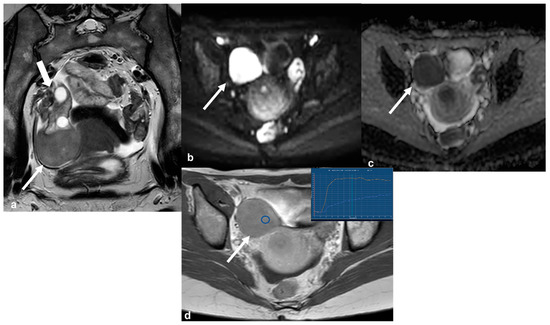

2.2.3. Pelvic Inflammatory Disease—Tubo-Ovarian Abscess (TOA)

2.3.5. Metastases